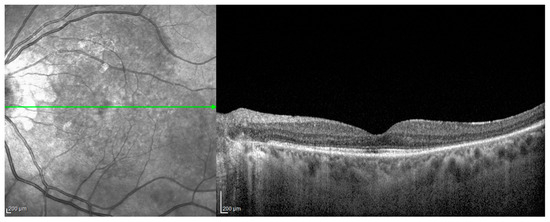

- Acute uveitic stage: This appears a few days after the prodromal phase and lasts for several weeks. During this period, the patient mainly complains of blurred vision, pain and central scotoma, and most patients present with bilateral posterior uveitis. The first sign is the thickening of the posterior choroid manifested as an elevation of the peripapillary retinochoroidal layer, hyperaemia and oedema of the optic disc [31,32] and circumscribed retinal oedema. The choroidal inflammation eventually becomes multifocal with a diffuse breakdown of the RPE causing serous localised elevation of the retina that can rapidly become confluent, leading to a diffuse serous retinal detachment (SRD) [33]. The anterior segment of the eye can be affected immediately after the aforementioned clinical signs in untreated patients. It can be characterised by acute bilateral granulomatous iridocyclitis, mutton-fat keratic precipitates, iris nodules and anterior chamber shallowing due to ciliary body oedema that may lead to acute angle-closure glaucoma.

- Chronic recurrent stage: This manifests as recurrent, mainly anterior granulomatous uveitis. Nevertheless, a thorough examination of the choroid at this stage with indocyanine green angiography (ICGA) or enhanced-depth imaging (EDI) and optical coherence tomography (OCT) might also find signs of active choroiditis [35]. These episodes of granulomatous uveitis are often resistant to corticosteroid therapy and may be characterised by iris mnodules, focal pigment atrophy of the iris and ocular hypotony. This is the stage where the complications of chronic inflammation, such as glaucoma, cataracts, neovascularisation of the retina and disc, subretinal fibrosis and subretinal neovascularisation, usually develop [36].